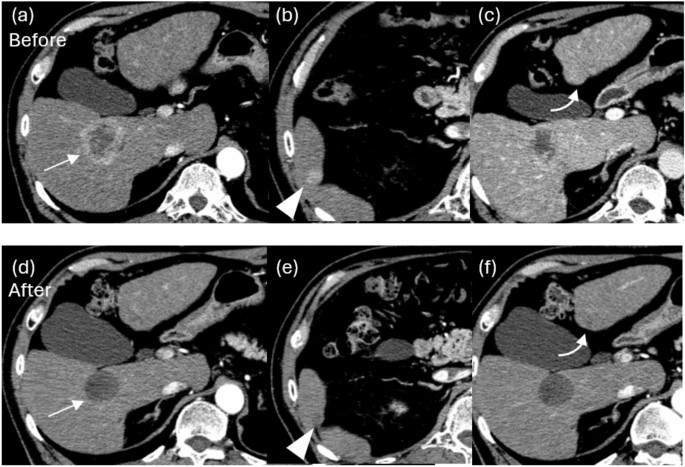

Arterial phase of contrast-enhanced CT before (a, b, c) and after (d, e, f) BOAI-TACE in a 70-year-old man. Three hepatocellular carcinomas (HCCs) were found in the liver, including a 45 mm HCC in S6 (a, arrow). The contrast effect of a 45 mm HCC in S6 disappeared after treatment and complete response (CR) was achieved (d). (b, e) A 14 mm HCC in S6 was also achieved CR (arrowhead). (c, f) An HCC in S2 (curved arrow) did not achieve CR and the overall evaluation was partial response.